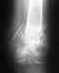

К сожалению, без повторной операции нету шансов на хороший исход. Фиксация винтами несостоятельна. Эндопротезирование, видимо, оптимальный путь.